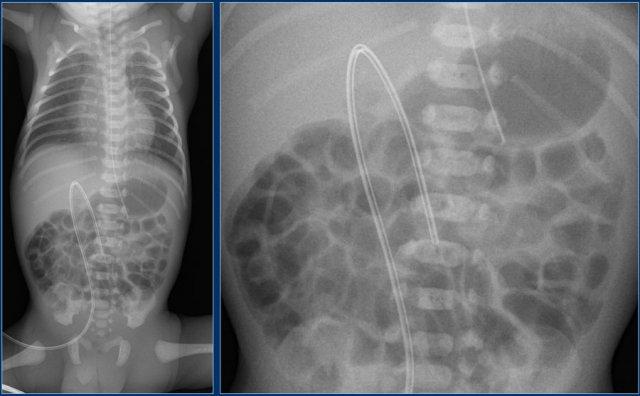

Đường truyền động mạch rốn (5)

Các phát hiện bao gồm:

- Đặt sai vị trí đường truyền động mạch rốn vào động mạch chậu trái.

- Đường truyền tĩnh mạch rốn ở vị trí quá sâu, đầu catheter nằm trong nhĩ phải.

- Ống thông dạ dày ở vị trí tốt.